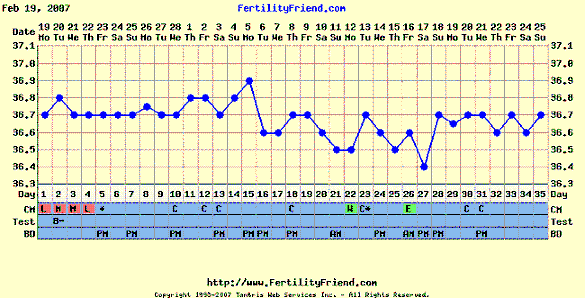

Gaby, hát ez nagyon ígéretes

, ha holnap megint felugrik én már nem mondok semmit, úgyis tudni fogod mire gondolok